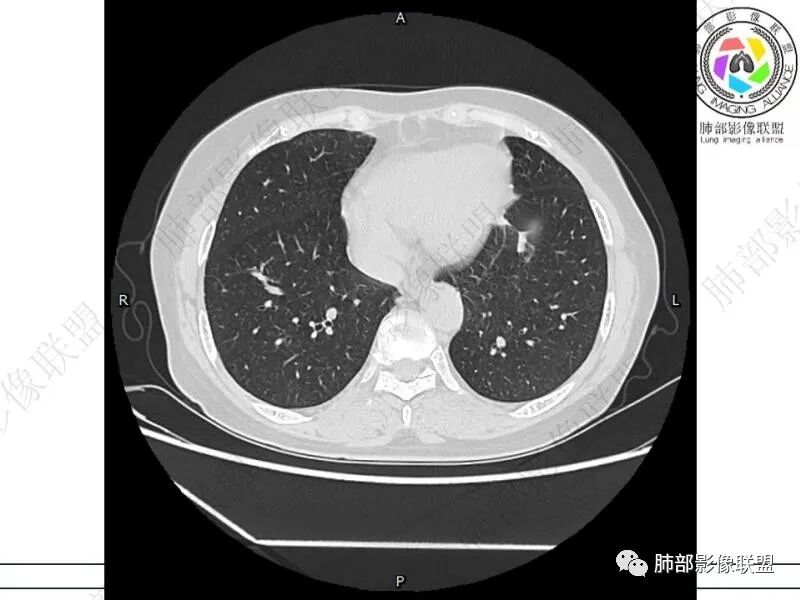

谢加平:结肠癌术后史,两肺胸膜下多发结节及斑块实变病灶,实边边界平直征(亚急性和慢性病变过程),双肺下叶后基底段胸膜下为甚,与胸膜平行特点,见支气管充气征,边缘模糊的GG0,首诊2022年11月18日肺部CT,与治疗11月28日对比,病灶未吸收,双肺下叶胸膜下病灶有侧向融合特点,综合分析符合炎性肉芽肿,隐球菌感染。

冰柠雨露:双肺多发小结节,斑片灶,复查双上小结节有的缩小变性,双下叶病灶增大,内见支气管像,抗感染效果不好,荚膜阴性,支气管灌洗未检出细菌,非感染性病变?淋巴瘤?

老年女性,结肠癌术后。两下肺胸膜下为主片状实变,右下肺短期复查融合且病灶长轴平行于胸膜,实变内可见支气管充气征,边缘磨玻璃晕,另两肺内胸膜下散在数枚小结节状、楔形实性灶。考虑感染性病变,隐球菌可能,鉴别肺转移。

2.影像特征:双肺胸膜下多发实性结节、磨玻璃影及实变影,胸膜下优势分布、晕征、胸膜下脂肪间隙存在,部分病灶边界平直征,有侧向融合趋势。

3.CEA复查1.8ng/ml,常规情况,基本排除转移。广谱抗生素治疗后无效,病灶仍然进展,考虑特殊感染。